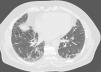

Tomografía computarizada de alta resolución de tórax en donde se observan opacidades reticulares subpleurales con bronquiectasias de tracción e imágenes de panal subpleural de predominio en lóbulos superiores. No se observa atrapamiento aéreo valorable en las secciones en espiración. Todo ello correspondería a un patrón consistente con neumonía intersticial usual (según los criterios del Consenso ATS/ERS/JRS/ALAT sobre el diagnóstico y manejo de fibrosis pulmonar idiopática, 2011).

Hacía un año había presentado dolor centrotorácico pleurítico, fiebre, tos seca y disnea progresiva, orientándose inicialmente como una fibrosis pulmonar idiopática. Se eliminaron las posibles exposiciones domésticas, se trató con prednisona 30mg/día durante 3 meses y, posteriormente, con N-acetilcisteína 1.800mg/día, a pesar de lo cual el paciente empeoró clínicamente. En la exploración física destacaban crepitantes en la auscultación pulmonar y acropaquia. Los marcadores de autoinmunidad eran normales. Solo destacaban IgG elevadas frente a Aspergillus fumigatus y Penicillium spp. Las pruebas funcionales respiratorias objetivaban un volumen espiratorio forzado en el primer segundo del 62%, capacidad vital forzada del 62%, índice del 76%, volúmenes pulmonares globalmente disminuidos y capacidad de transferencia de CO del 54%. Presentaba hipoxemia moderada con normocapnia. En la prueba de la marcha caminó 600m con una caída de la saturación de oxígeno hasta el 87%. La tomografía axial computarizada mostró un patrón inconsistente con una neumonía intersticial usual (fig. 1). Se decidió realizar un lavado broncoalveolar, que mostró una celularidad con predominio de neutrófilos y una criobiopsia de pirámide basal derecha. El examen histológico mostró un parénquima pulmonar con cambios reactivos de predominio histiocitario intersticial sugestivos de neumonitis por hipersensibilidad.